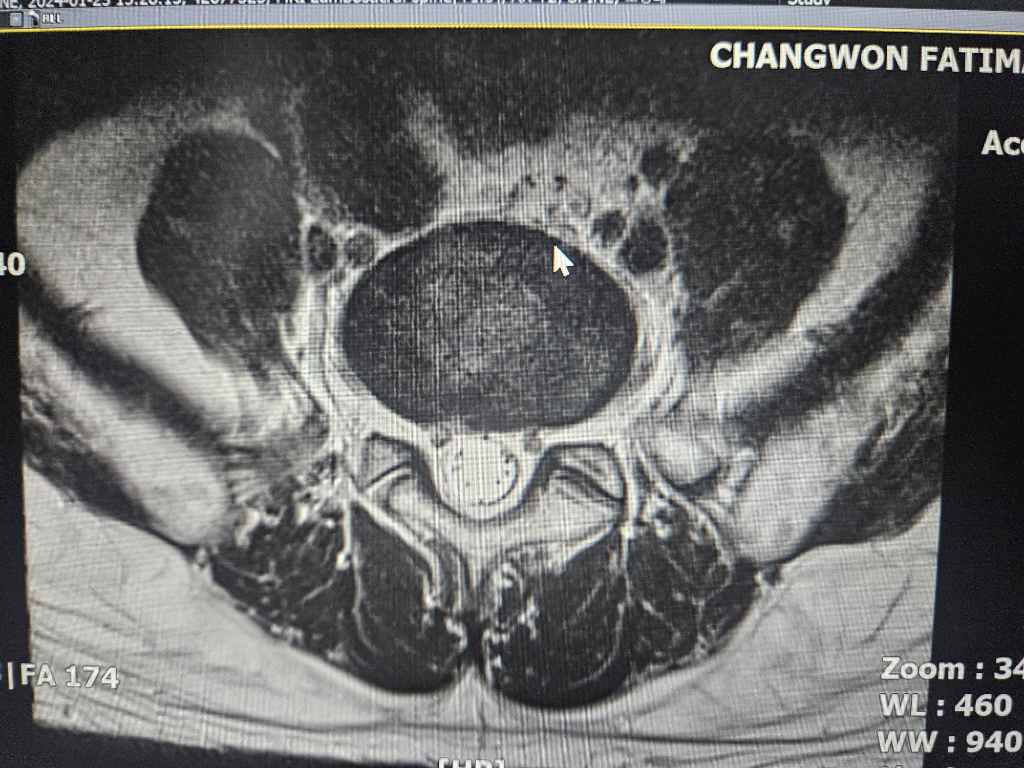

수술해야될 정돈지 사진보시고 확인좀 해주세요

척추분리증과 전방전위증등으로 통증이 너무심한데

허리부터 다리까지 통증이 있고 종아리까지 전기가 찌릿한 증상 누워있을때는 그나마 참을만 한데 그외 다른자세를 하면 통증이 심해집니다

걷는것도 10분이상하면 허리 부터 허벅지 까지 통증이 심하게 생깁니다

척추분리증은 30년 정도 되었고 다른건 10년이 넘은거 같습니다

약이나 물리치료도 오래 했지만 지금은 효과도 없고 시술또한 별다른 효과가 없어서 통증으로 인한 예민함과 잠잘때 힘이들어 정신과약을 복용중입니다

사진과함께 증상을 종합해봤을때 수술이 필요한지 아니면 보존치료가 더 나은지 궁금 합니다

보내주신 사진만으로는 정확한 진단을 내리기 어렵습니다. 정확한 진단을 위해서는 전문의의 진찰과 검사가 필요합니다. 하지만 사진과 증상을 종합해보면 수술을 고려해볼 수 있는 수준으로 보입니다.

척추분리증과 전방전위증은 척추뼈가 정상적인 위치에서 벗어나 발생하는 질환입니다. 이 질환은 허리와 다리에 통증, 저림, 감각 이상 등의 증상을 유발할 수 있습니다.